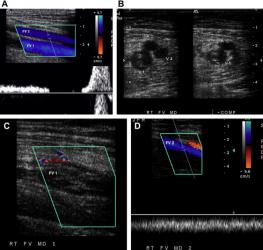

CƠ CHẾ SINH LÝ BỆNH GÂY SUY TĨNH MẠCH

Nhiều cơ chế khác nhau góp phần làm suy yếu van tĩnh mạch nông.

- Thường gặp nhất là yếu thành tĩnh mạch bẩm sinh, tĩnh mạch giãn dưới áp lực bình thường dẫn đến suy tĩnh mạch thứ phát.